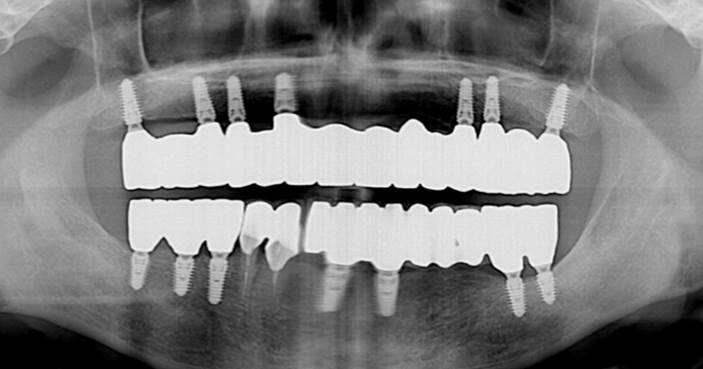

Clinical case: A Full transition from natural teeth to all-on-6 bridges

with AnyRidge implants

- Courtesy of Dr. Rabih Abi Nader, UAE -

“AnyRidge shows excellent esthetic results

with Zirconia prosthesis in full-mouth rehabilitation case . ”